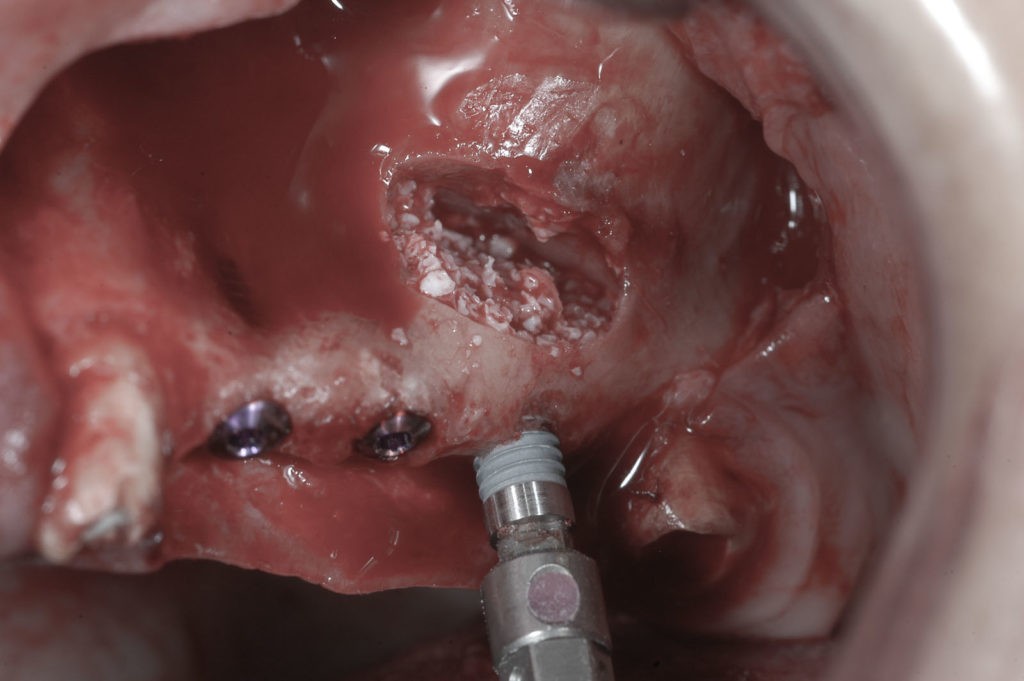

Zabieg odbudowy zębodołu powinno się wykonać możliwe jak najszybciej po usunięciu zęba. Jego celem jest odbudowa naturalnej objętości kości w miejscu utraconego zęba, a następnie szybkie wprowadzenie implantu. Najlepsze rezultaty uzyskuje się przy zastosowaniu biomateriału w formie bloczków kolagenowych lub granulatu, które dają trwałe efekty odbudowy oraz optymalną funkcję i estetykę odtworzonych koron zębów na wszczepionym implancie.

Procedury te są stosowane w sytuacji niedostatecznej ilości kości, skutkującej odsłonięciem gwintu, podczas gdy wszczepiamy implanty stomatologiczne lub też jako zabiegi poprzedzające ich wprowadzenie.​

Zabiegiem, który rozwiązuje ten problem, jest podniesienie dna zatoki szczękowej, czyli odbudowa kostna w okolicy zębów trzonowych. Ubytek kości uzupełniany jest materiałem kościotwórczym, który układany jest pod błoną wyścielającą zatokę szczękową, zwaną membraną Schneidera. Zmniejszając objętość zatoki szczękowej, tworzy się tym samym stabilną strukturę kostną, umożliwiającą zabieg implantacji wszczepów śródkostnych.